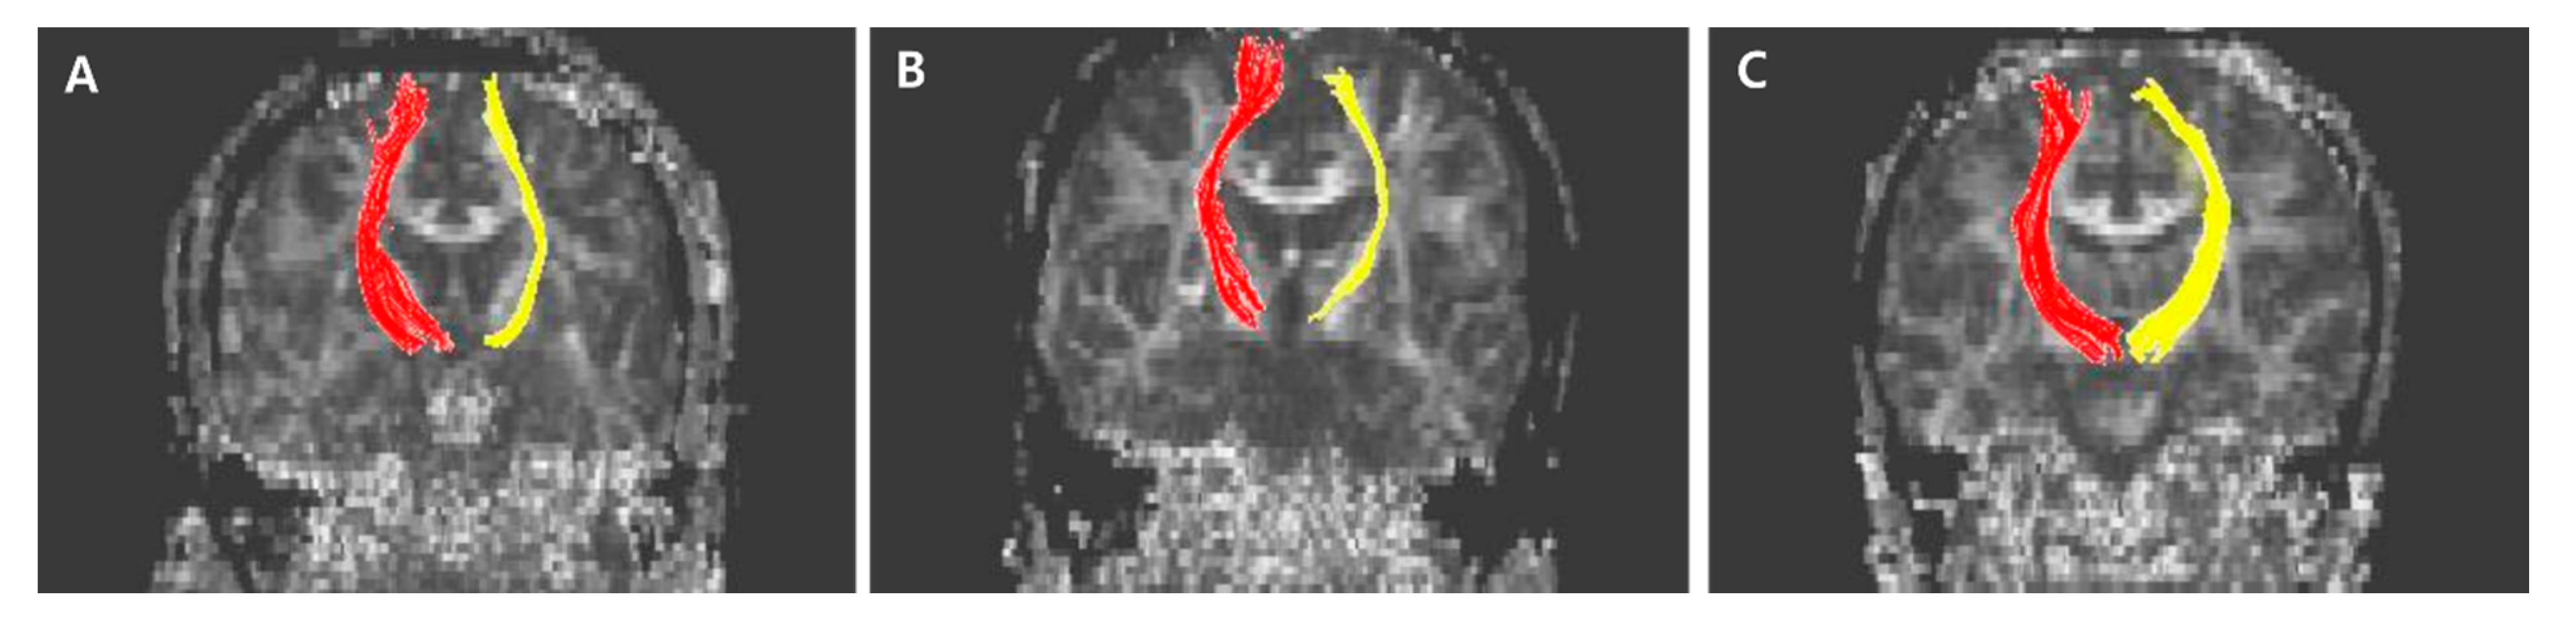

The normalized FA values of STT in the CPSP group were lower than those in the stroke control group and normal control groups; 0.79 for CPSP, 0.98 for non-CPSP, 0.98 for control (Figure 2A). The normalized FA values of STR in the CPSP group were lower than those in the stroke control group and normal control groups; 0.88 for CPSP, 1.00 for non-CPSP, 0.97 for control (Figure 2B). There were no differences in the FA values of STT and STR between the stroke control and normal control groups. The normalized FN values of STT and STR were lower in the CPSP and stroke control group than in the normal control group. However, there was no significant difference between the CPSP and stroke control for the normalized FN of STT and STR. Representative DTIs of STT in all three groups are shown in Figure 3, and those of STR in Figure 4.

Figure 4. Representative diffusion tensor tractography images of superior thalamic radiation in typical subjects from the (A) CPSP group, (B) stroke control, and (C) normal control groups. The non-affected tract is shown in red, and the affected tract in yellow.